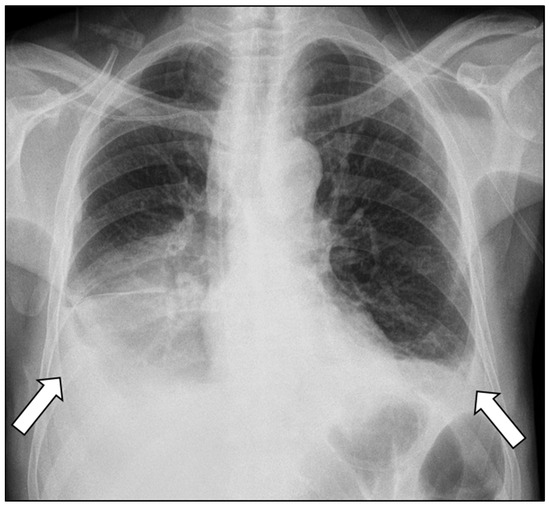

Bilateral Pancreaticopleural Fistula Masquerading as Thoracic Disease in Chronic Calculous Pancreatitis

Background: Pancreaticopleural fistula is a rare complication of chronic pancreatitis resulting from pancreatic duct disruption, typically presenting with pleural effusion and predominant respiratory symptoms. Bilateral pleural involvement is exceptionally uncommon and poses significant diagnostic and therapeutic challenges. Case Presentation: A 56-year-old [...] Read more.

Background: Pancreaticopleural fistula is a rare complication of chronic pancreatitis resulting from pancreatic duct disruption, typically presenting with pleural effusion and predominant respiratory symptoms. Bilateral pleural involvement is exceptionally uncommon and poses significant diagnostic and therapeutic challenges. Case Presentation: A 56-year-old man with a history of chronic alcohol abuse presented with progressive dyspnea and mild epigastric pain. Imaging revealed bilateral pleural effusions, an atrophic pancreas with a markedly dilated main pancreatic duct containing calculi, and a fistulous tract extending from the pancreatic body through the esophageal hiatus into the mediastinum. Magnetic resonance cholangiopancreatography confirmed the diagnosis of chronic calculous pancreatitis complicated by a pancreaticopleural fistula. After unsuccessful conservative management, the patient underwent distal pancreatectomy, resection of the fistulous tract, and Roux-en-Y pancreatojejunostomy. The postoperative course was uneventful, with complete resolution of pleural effusions and sustained clinical improvement. Conclusions: This case highlights the importance of considering pancreaticopleural fistula in patients with unexplained pleural effusions and minimal abdominal symptoms, particularly in the context of chronic pancreatitis. Bilateral involvement, although rare, should not preclude timely diagnosis. Appropriate diagnostic studies by computed tomography, magnetic resonance imaging, and magnetic resonance cholangiopancreatography are crucial for establishing the diagnosis. Surgical management offers definitive treatment in patients with ductal obstruction and calculous disease, resulting in excellent long- term outcomes. Full article